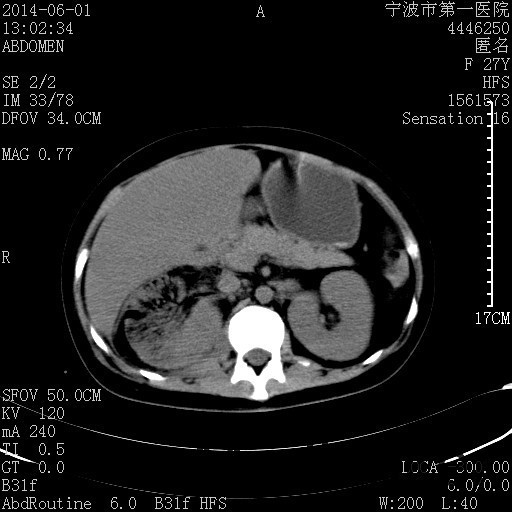

患者,女,27岁,因“右下腹疼痛伴呕吐2天”入院 患者无明显诱因出现右下腹疼痛伴呕吐、发热,体温最高39度,急诊CT示:右肾集气,考虑气性肾盂肾炎。

查体: 右肾区叩击痛,右下腹压痛,无反跳痛。 辅助检查: 空腹血糖9.7mmo/L,餐后血糖18mmol/L 血常规:白细胞 11.3*109/L, 中性百分比 77.4%, 血红蛋白 8g/L, 血小板 319*109/L 尿常规 WBC+++ 生化:白蛋白 37.5g/L,肝肾功能正常 泌尿系CT:右肾集气

诊断为“气性肾盂肾炎,感染性休克,糖尿病酮症酸中毒” 血、尿、脓液培养均示“克雷伯杆菌” 入院第2天行“右双J管置入术” 入院第3天、7天行“右肾穿刺造瘘术” 入院1月行“右肾切除术” 术后顺利康复出院。